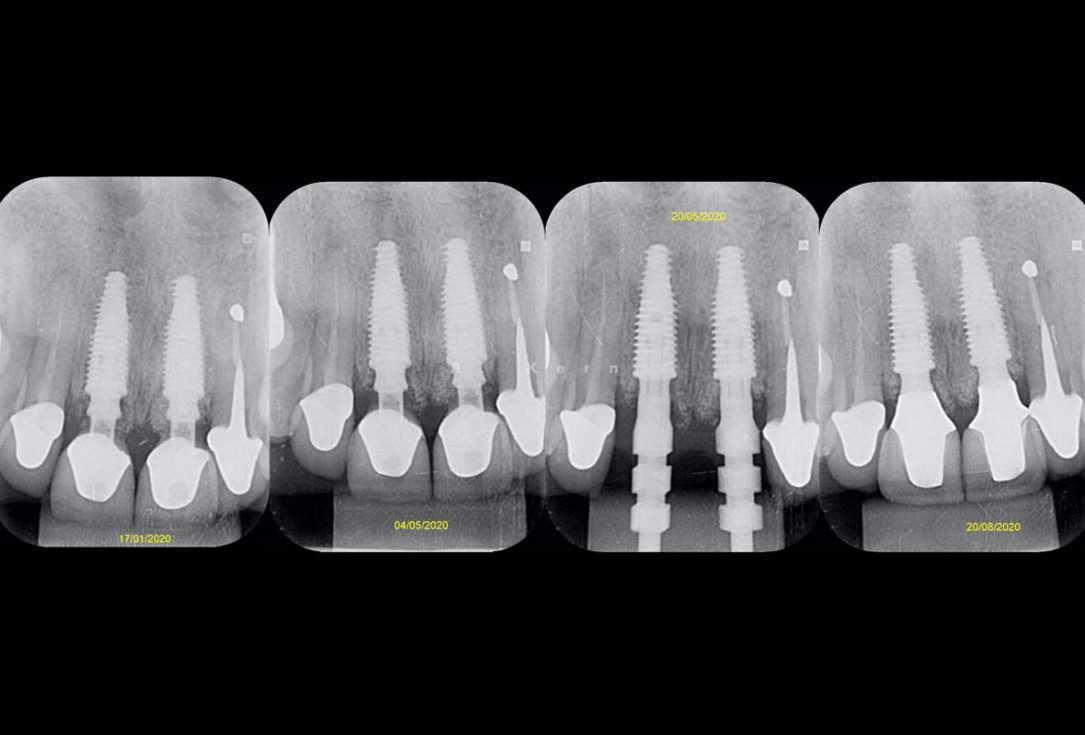

12/12 - Radiographic follow-up

Immediate implant placement and periimplant bone augmentation using cerabone® - Dr. R. Kern